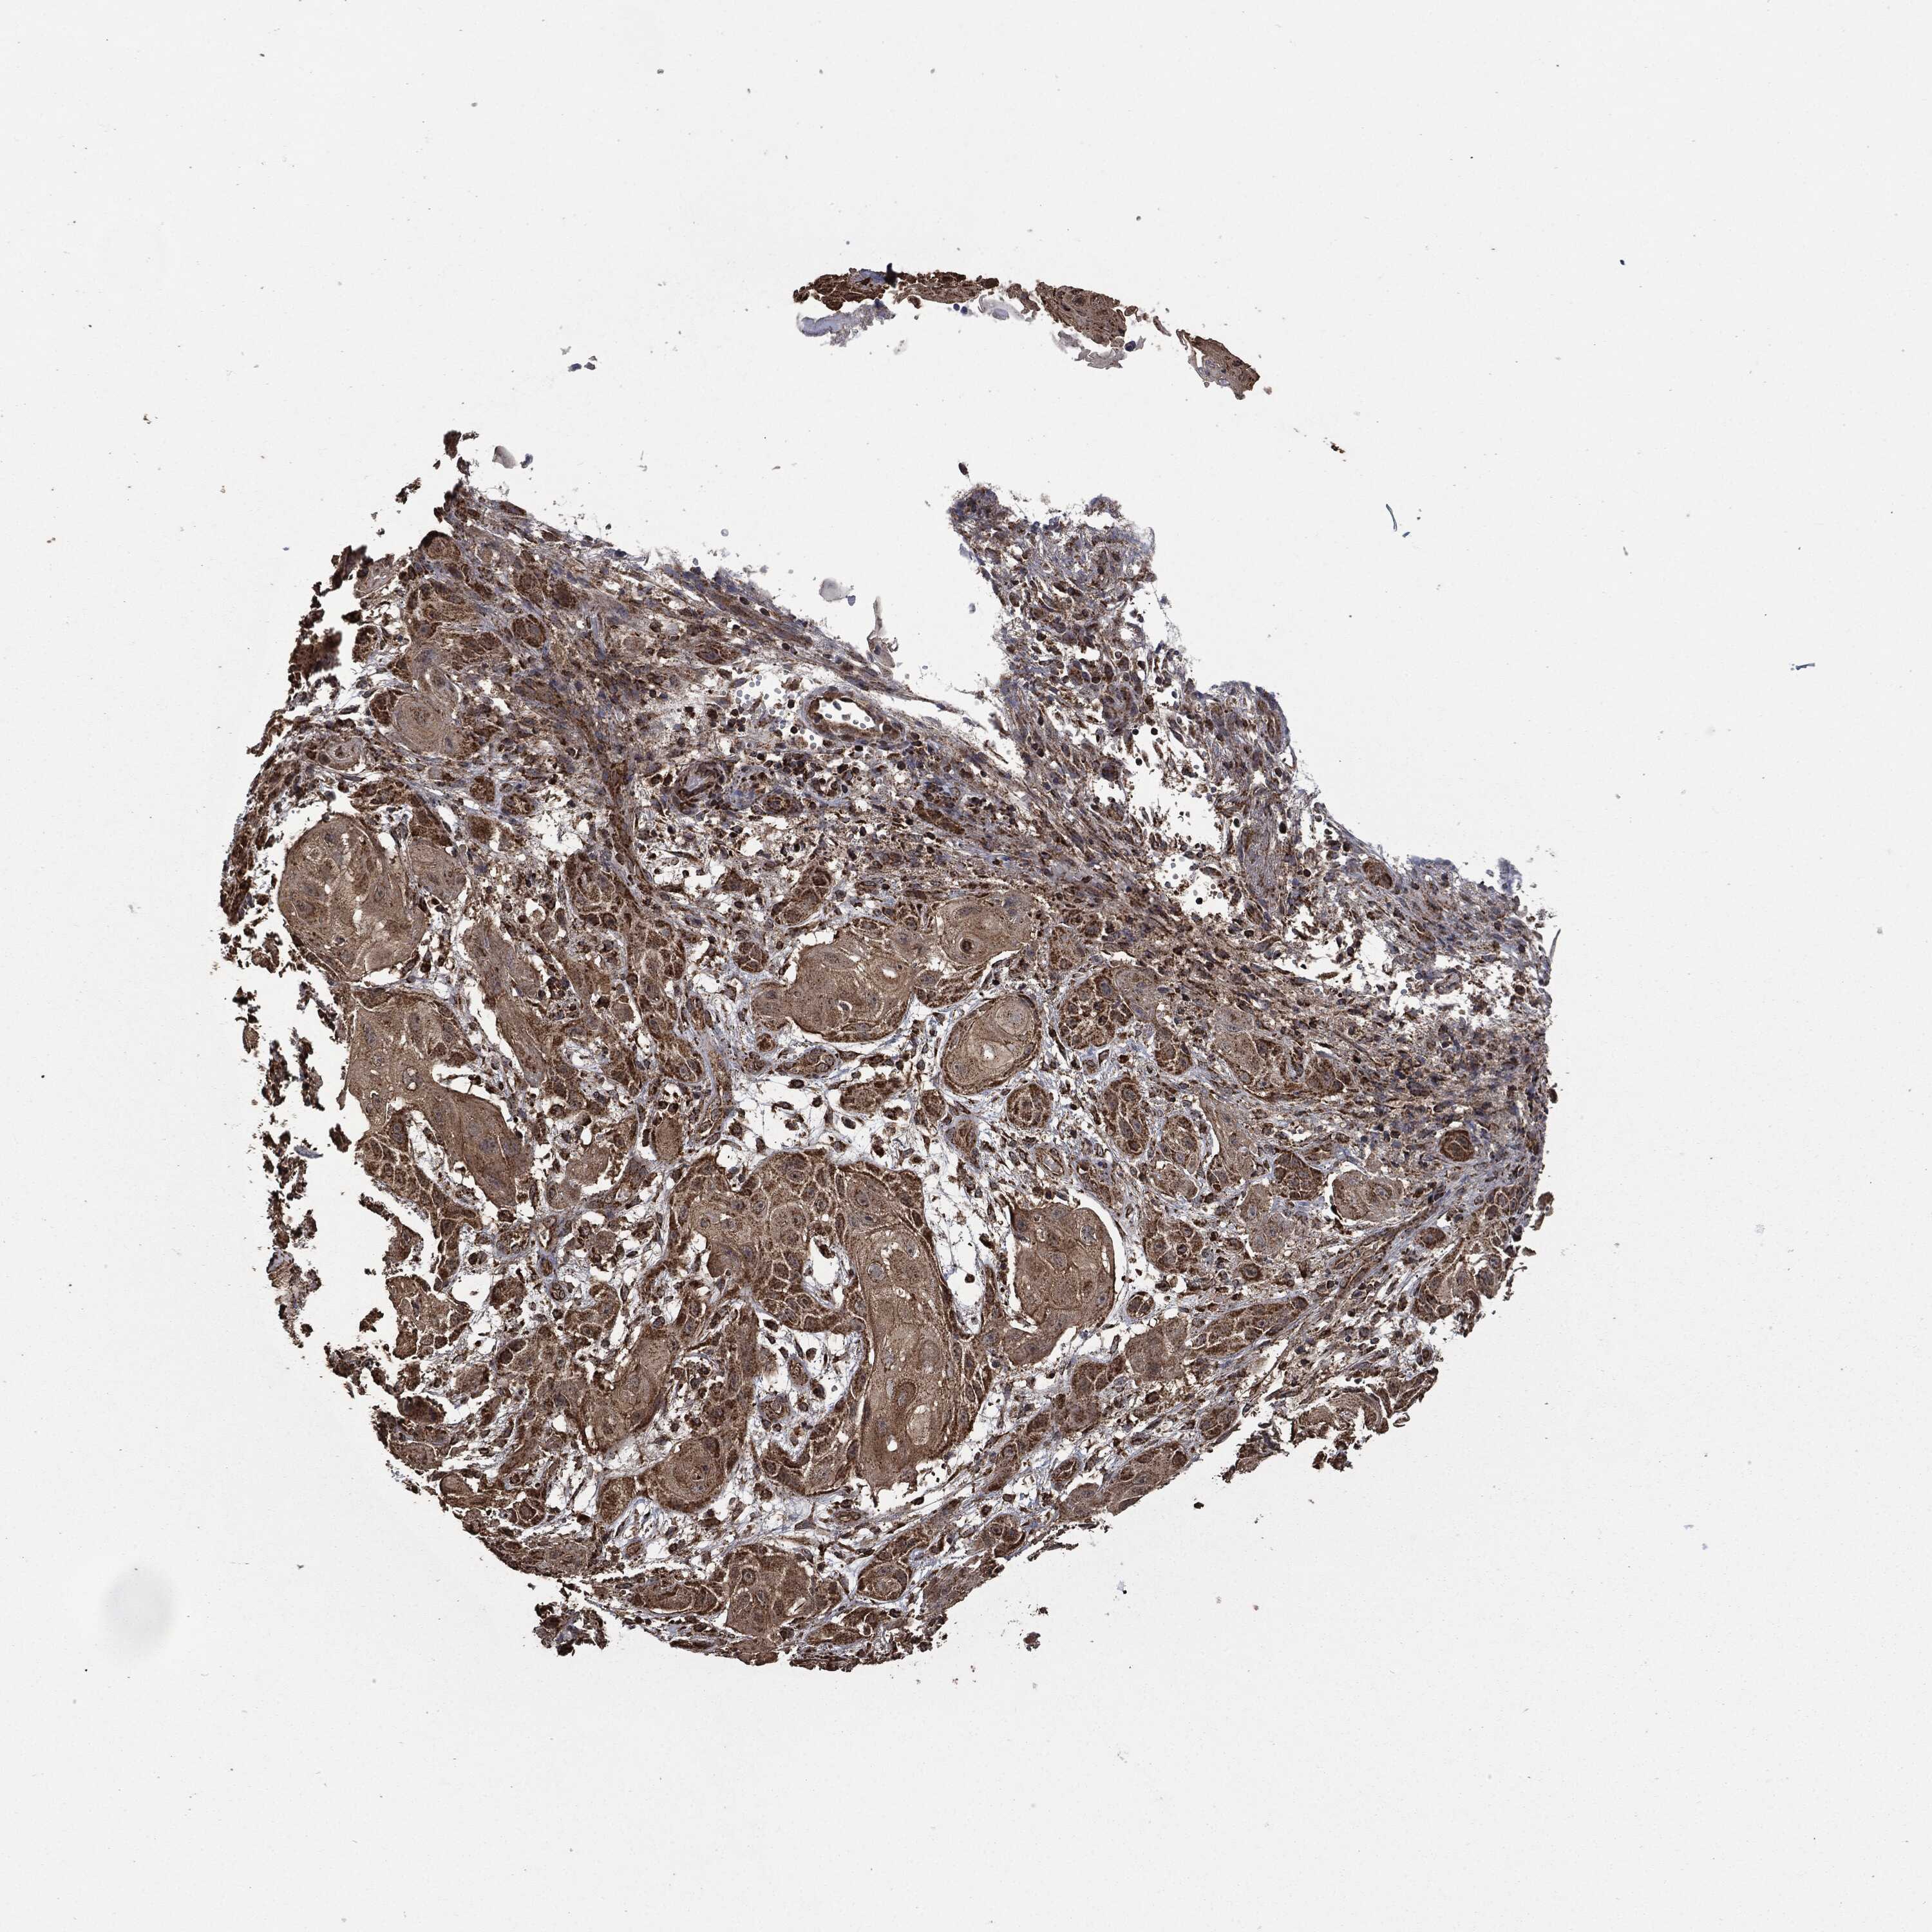

SKIN CANCER - Protein expressioni

A mouse-over function shows sample information and annotation data. Click on an image to view it in a full screen mode. Samples can be filtered based on level of antibody staining by selecting one or several of the following categories: high, medium, low and not detected. The assay and annotation is described here.

Antibody stainingi

Antibody staining in the annotated cell types in the current human tissue is reported as not detected, low, medium, or high, based on conventional immunohistochemistry profiling in selected tissues. This score is based on the combination of the staining intensity and fraction of stained cells.

Each image is clickable and will lead to virtual microscopy that enables deeper exploration of all samples and also displays staining intensity scores, fraction scores and subcellular localization as well as patient and tissue information for each sample.

Antibody HPA006723

Antibody CAB080348

Staining

High

Medium

Low

Not detected

Intensity

Strong

Moderate

Weak

Negative

Quantity

>75%

75%-25%

<25%

None

Location

Nuclear

Cytoplasmic/membranous

Cytoplasmic/membranous,nuclear

Squamous cell carcinoma, NOS

Squamous cell carcinoma, metastatic, NOS

Basal cell carcinoma

Papilloma, NOS